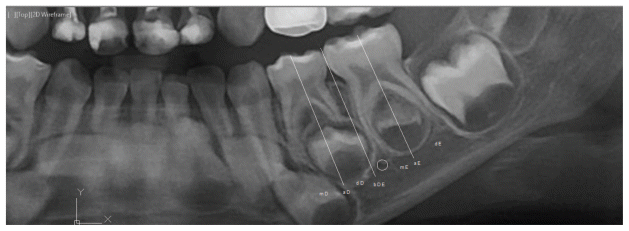

Measurement of the Vertical Location of the MF:

The vertical position of the mandibular foramen (MF) was ascertained by measuring the distance from the alveolar crest to the inferior border of the mandible. A line was constructed from the center of the MF perpendicular to the inferior border of the mandible, extending to the alveolar crest. This measurement was divided into three equal parts, and the position of the MF was documented as illustrated in Figure 2 (6):

- Upper one-third.

- Middle one-third.

- Lower one third